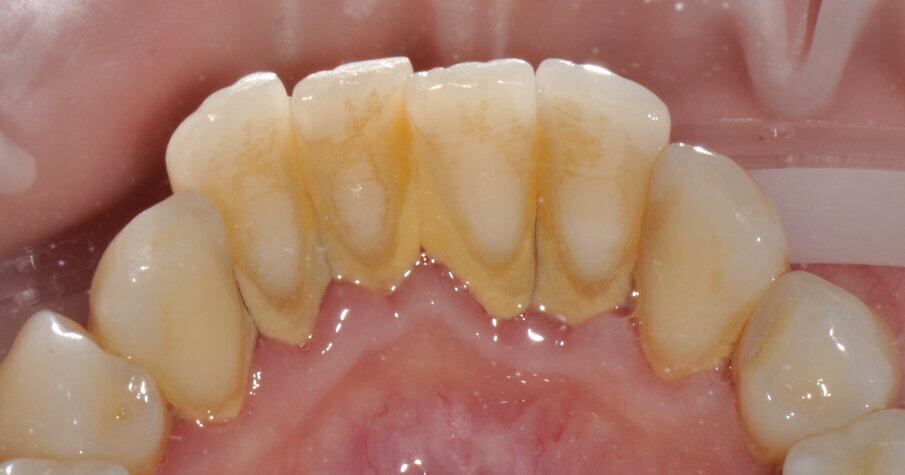

- Applicazione del rilevatore di placca bifasico: permette la distinzione fra i depositi di placca recenti da quelli meno recenti ( 1a-1c);

Figg. 1a-1c - Applicazione del rilevatore di placca che verrà usato come guida durante la terapia, nel versante vestibolare (1a), palatale (1b) e linguale (1c). Si noti lo scarso livello di igiene orale domiciliare e l’assenza di utilizzo dei presidi interdentali.